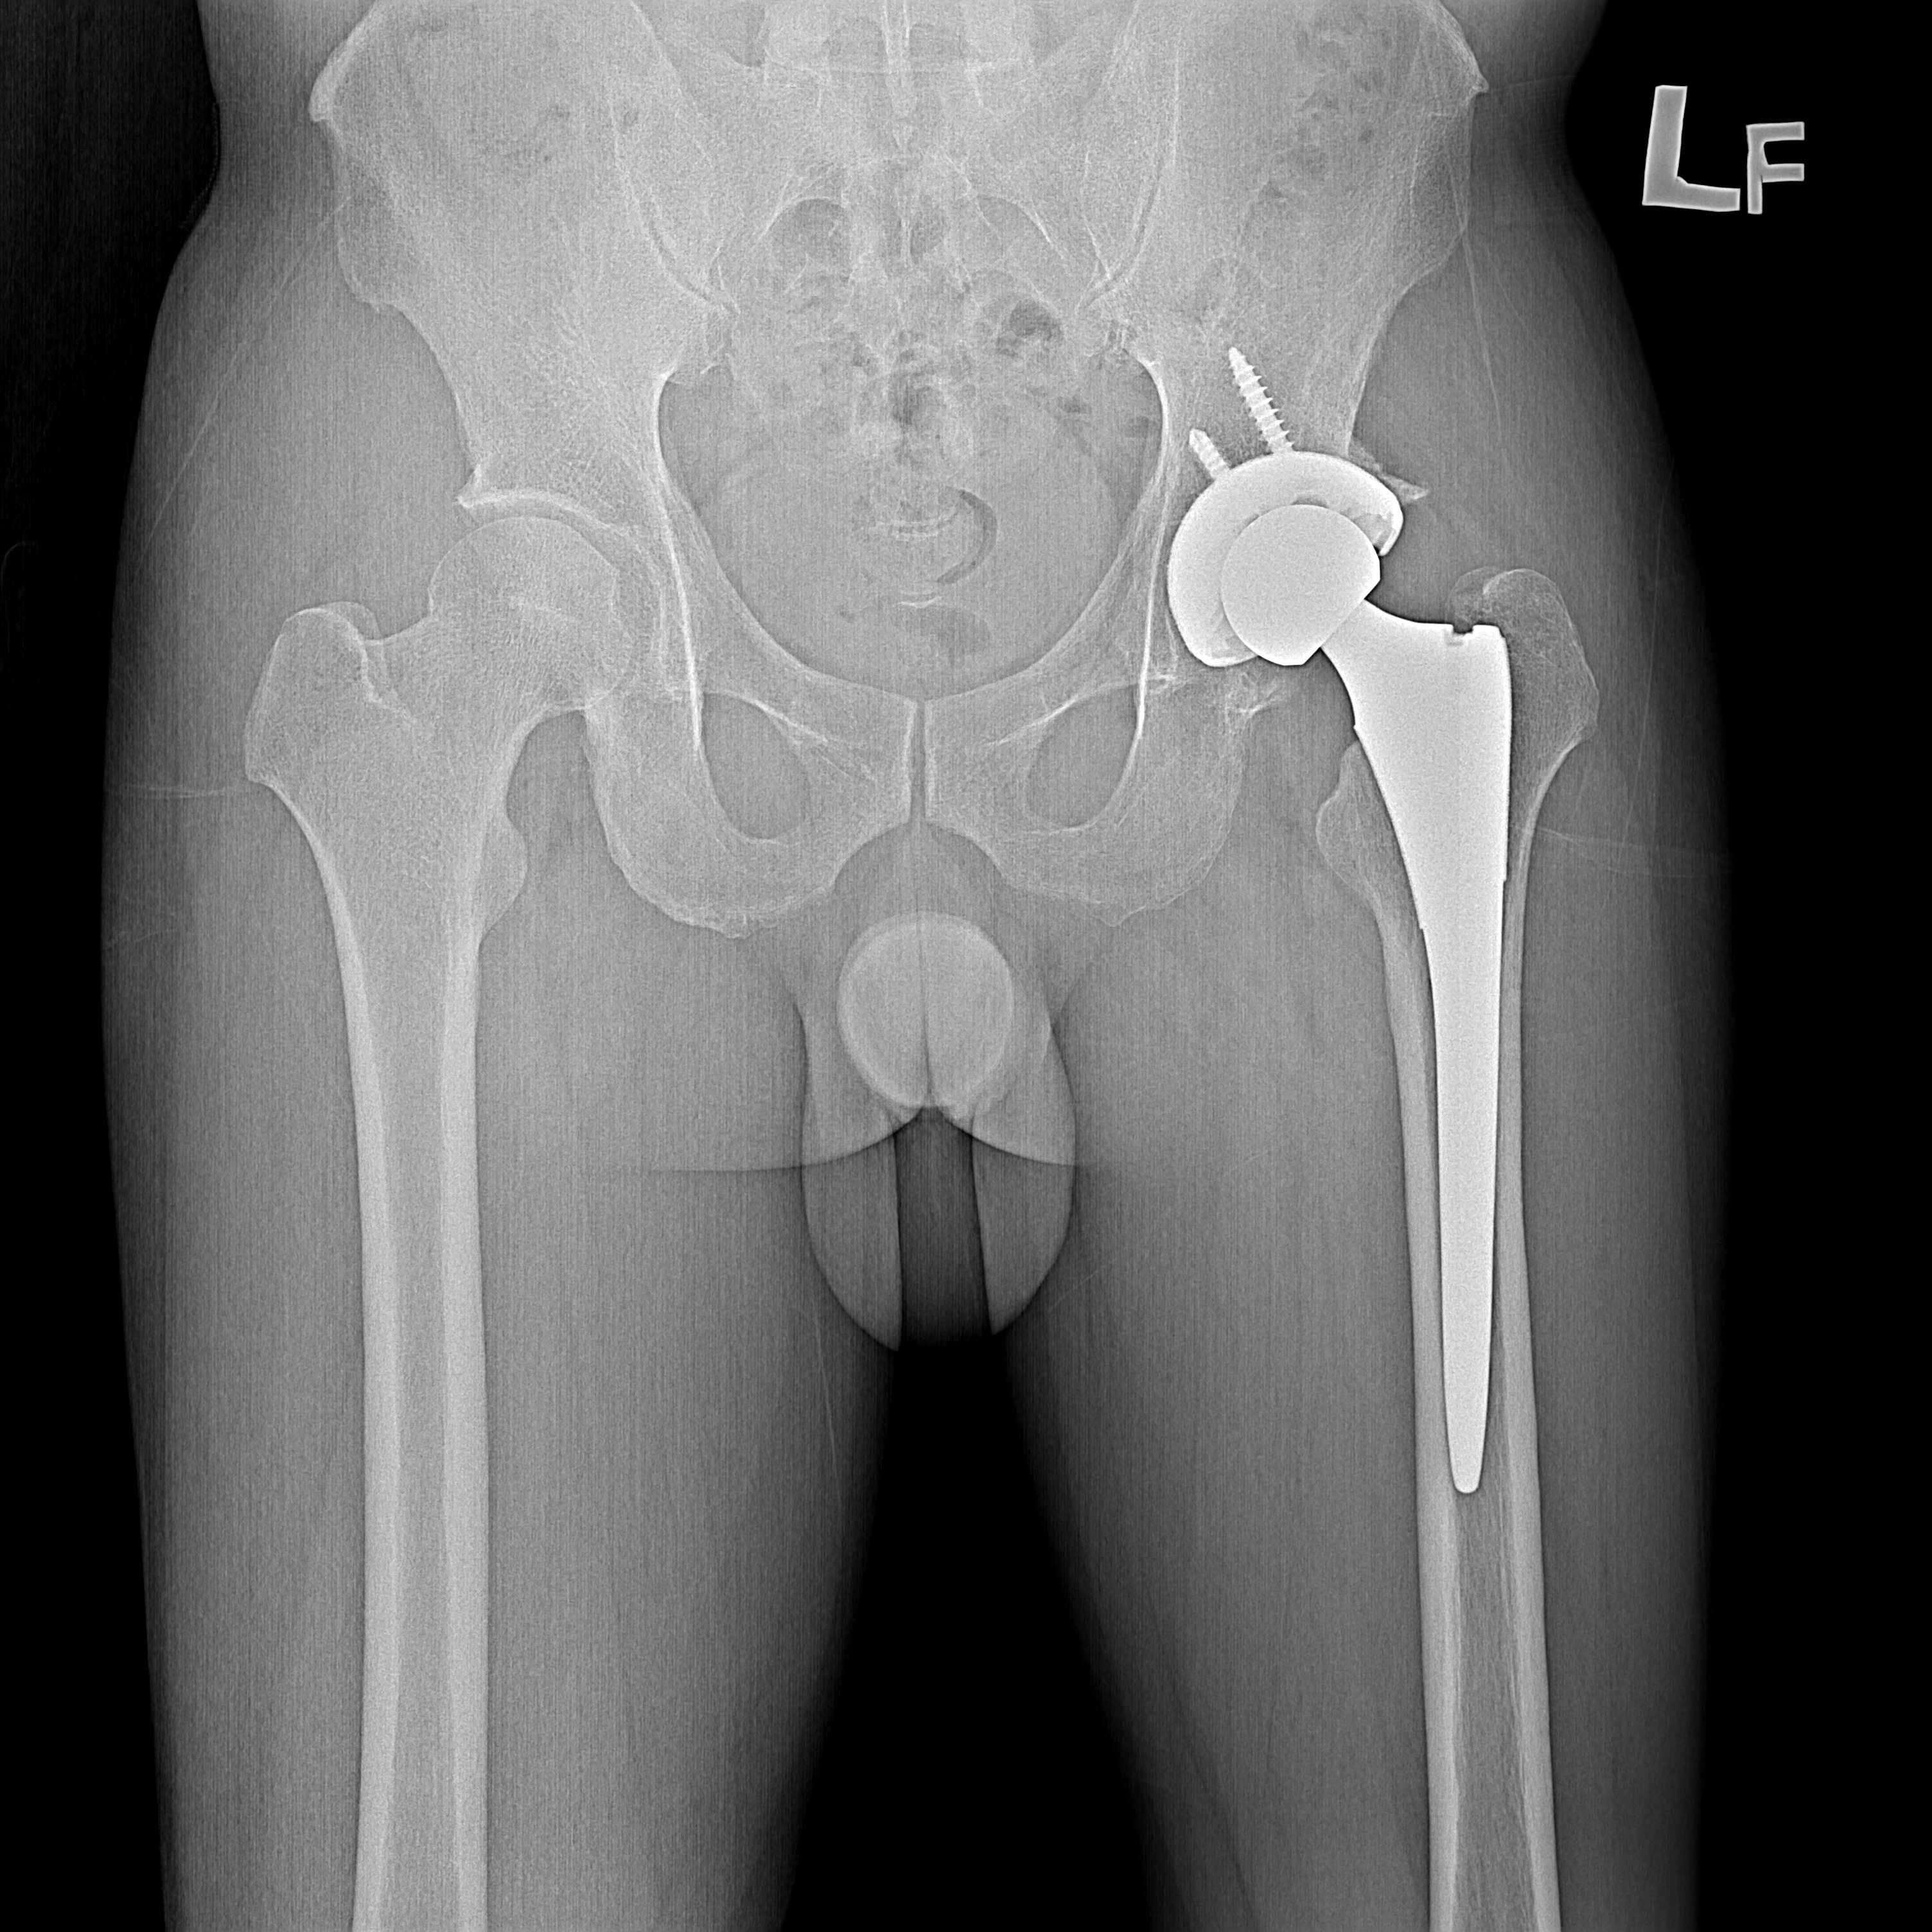

傳統髖關節置換 首頁 案例分享 髖關節手術 傳統髖關節置換 54歲蔡先生退化性關節炎 術前 術後 張女士 51歲 退化性關節炎(DDH先天發育不全 CROWE TYPE 2) 術前 術後 38歲林先生 退化性關節炎 術前 術後 72歲謝女士 退化性關節炎 術前 術後 71歲 謬女士 骨股頭壞死 術前 術後 50歲 郭先生骨股頭壞死 術前 術後 80歲 盧先生骨股頭壞死 術前 術後 林先生 37歲 術前 術後 邱女士 51歲 術前 術後 張女士 50歲 術前 術後